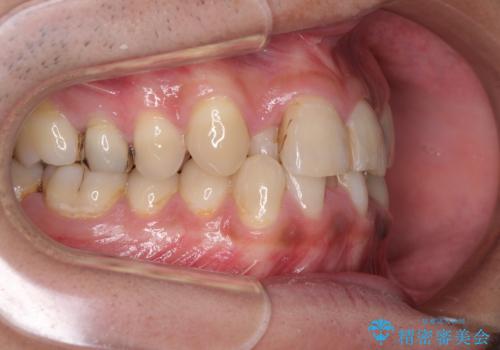

第二小臼歯抜歯の矯正治療は、治療期間が長引くことが多いですが、動きが非常に良く、予定の治療期間で終えることができました。

上下の正中も思っていた以上に良い位置に改善されました。